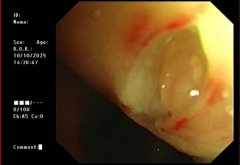

【精准“导航”+无痛定位】南通六院胸外科黑科技让“刁钻”肺结节无处可藏!

肺结节位置太深、藏在骨头缝里? 传统定位又疼又有辐射? 别担心!南通六院胸外科黑科技 CT三维数据融合式经皮穿刺导航定位术 2分钟精准锁定病灶,...